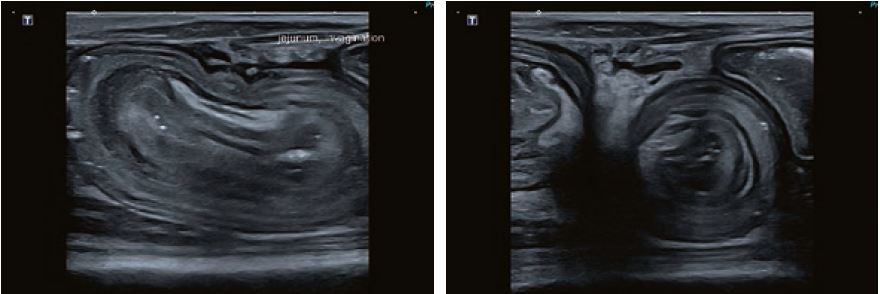

Випадок 2

Кішка, самиця, мейн-кун, два роки; на лікуванні від блювоти та схуднення протягом десяти днів; помірне збільшення обхвату при пальпації, УЗД кишківника з інвагінацією та затримкою газів; інтраопераційно: видалено 15 см кишківника; кішка почувається добре.